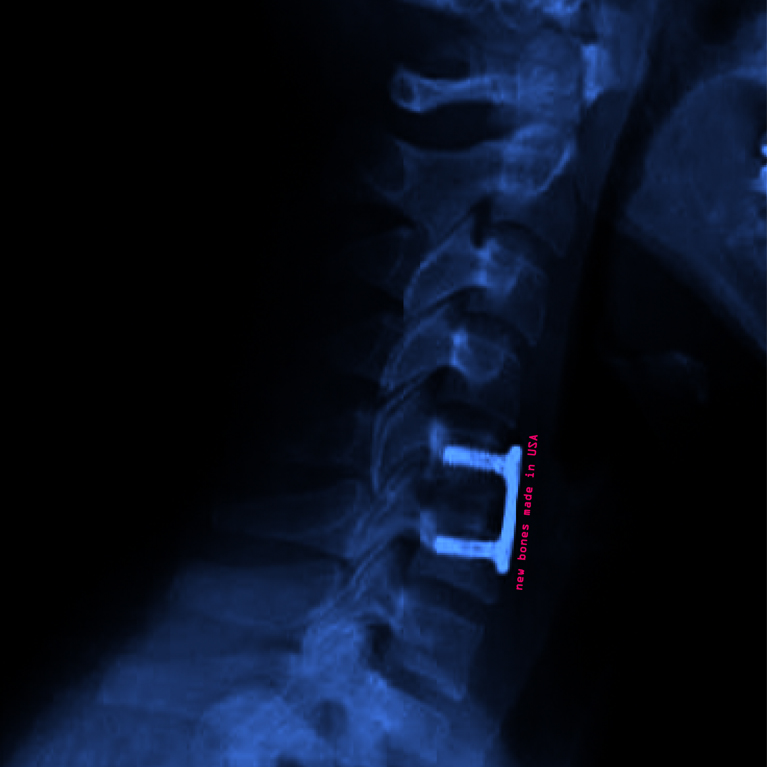

• 院1の最後の学期、Spring Quarter のさいごになって、生まれてこのかたずっと我慢していた左半身の痛みと痺れをなんとかするべく、Stanford Hospital で、首の頸椎をけずり、潰れた椎間板をはずし、ボーンバンクから新しい椎間板用の骨をもらって、メタルジョイントでとめるというすさまじい手術をしました。人生はなかなかカラフルです。そんなわけで、最後の学期はコンプリートできず、どうなることやら。(佐藤先生、ご無沙汰して申し訳ありません!元気で制作にも励んでおりますが、つぎからつぎへと、忙しいです。とはいえ、TAP のゼミでの共同制作は、参加したかったな。滑り台つくりたかった(滑りたかった???)。ちょっとくやしかったです。)

⇒志甫さん 久しぶりです!それにしても大手術ですね。手術によって身体が楽になると良いですね。それからmade in USA の写真、とってもカッコいい。赤く写っているということは、リアルは緑の文字なのだろうか? そうか、志甫さんは、9月入学で今が最終学期ですね。もう夏休み?忙しそうだけど、お元気で!! また冷やかしてください。sato